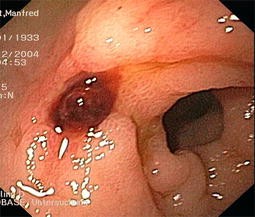

Abb. 2